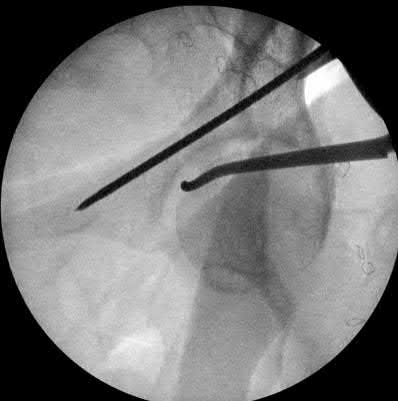

A 12-year-old obese boy presents with vague left thigh and knee pain. He is diagnosed with a Slipped Capital Femoral Epiphysis (SCFE) as seen in similar clinical scenarios.

During percutaneous in-situ fixation, unrecognized penetration of the guide wire into the hip joint occurs. What is the most likely specific complication resulting from this technical error?

Chondrolysis is a severe complication of SCFE characterized by rapid destruction of the articular cartilage. While it can occur idiopathically, its most established iatrogenic cause is unrecognized intra-articular hardware penetration. The 'approach-withdraw' fluoroscopic technique is required during pinning to assure pins are entirely intraosseous. Avascular necrosis (AVN) is usually due to damage to the epiphyseal blood supply (retinacular vessels) secondary to the initial displacement, forceful closed reduction, or posterosuperior pin placement.